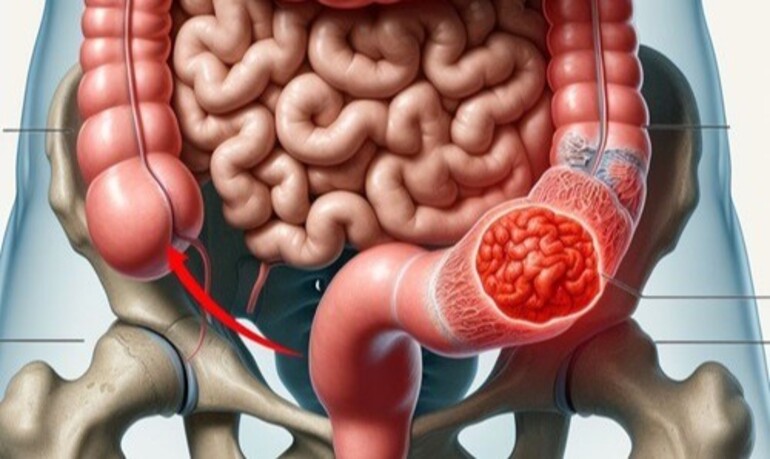

Laparoscopic Surgeries

Minimally invasive surgical procedures that use small incisions and a camera to perform operations with precision and faster recovery times.

- Minimally Invasive Techniques

- Faster Recovery

- Reduced Scarring

- Lower Risk of Infection

- Advanced Surgical Equipment

- Expert Consultation & Post-Operative Care